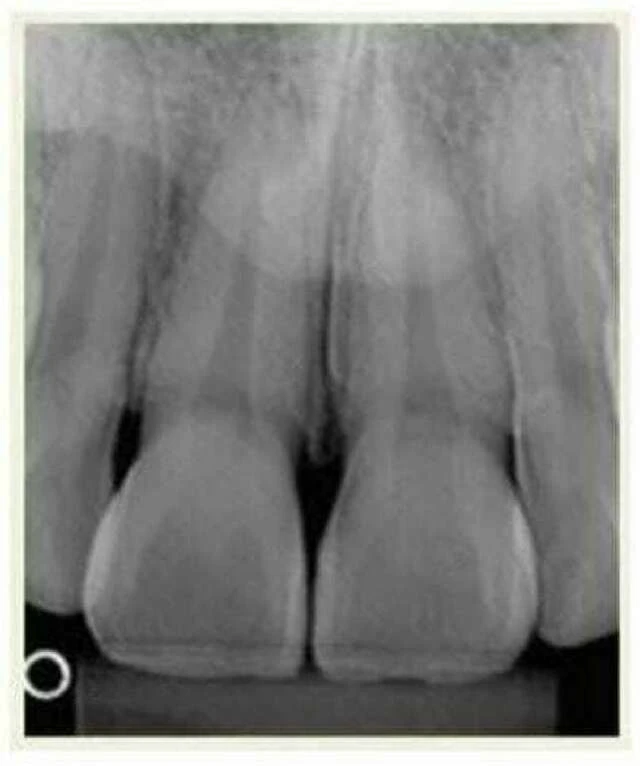

f. Phim cận chóp răng cửa dưới và trên: Phim này dùng so sánh trong suốt quá trình điều trị để xác định xem có tiêu chân răng hay không. Phim này định hình chiều dài chân răng.